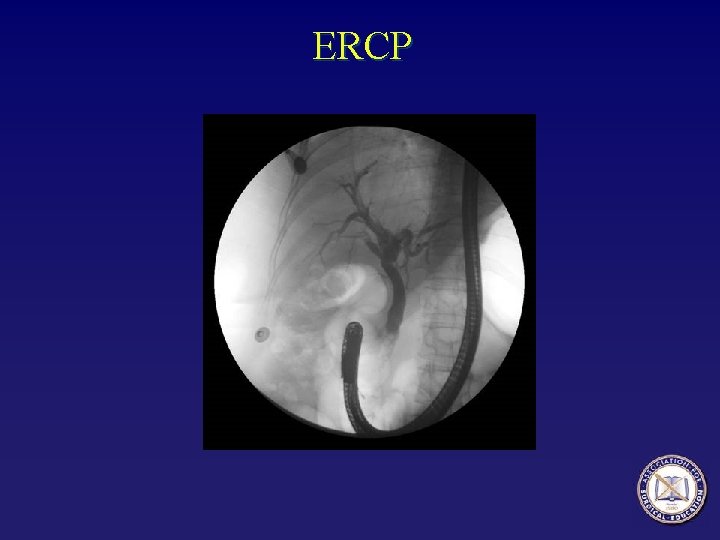

Timing of cholecystectomy • In patients with severe pancreatitis and an obstructed biliary tree secondary to choledocholithiasis, ERCP and sphincterotomy significantly reduce morbidity related to biliary complications but do not alter the course of the pancreatic inflammation.

ERCP